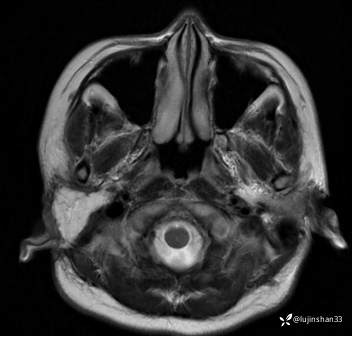

术后MRI: